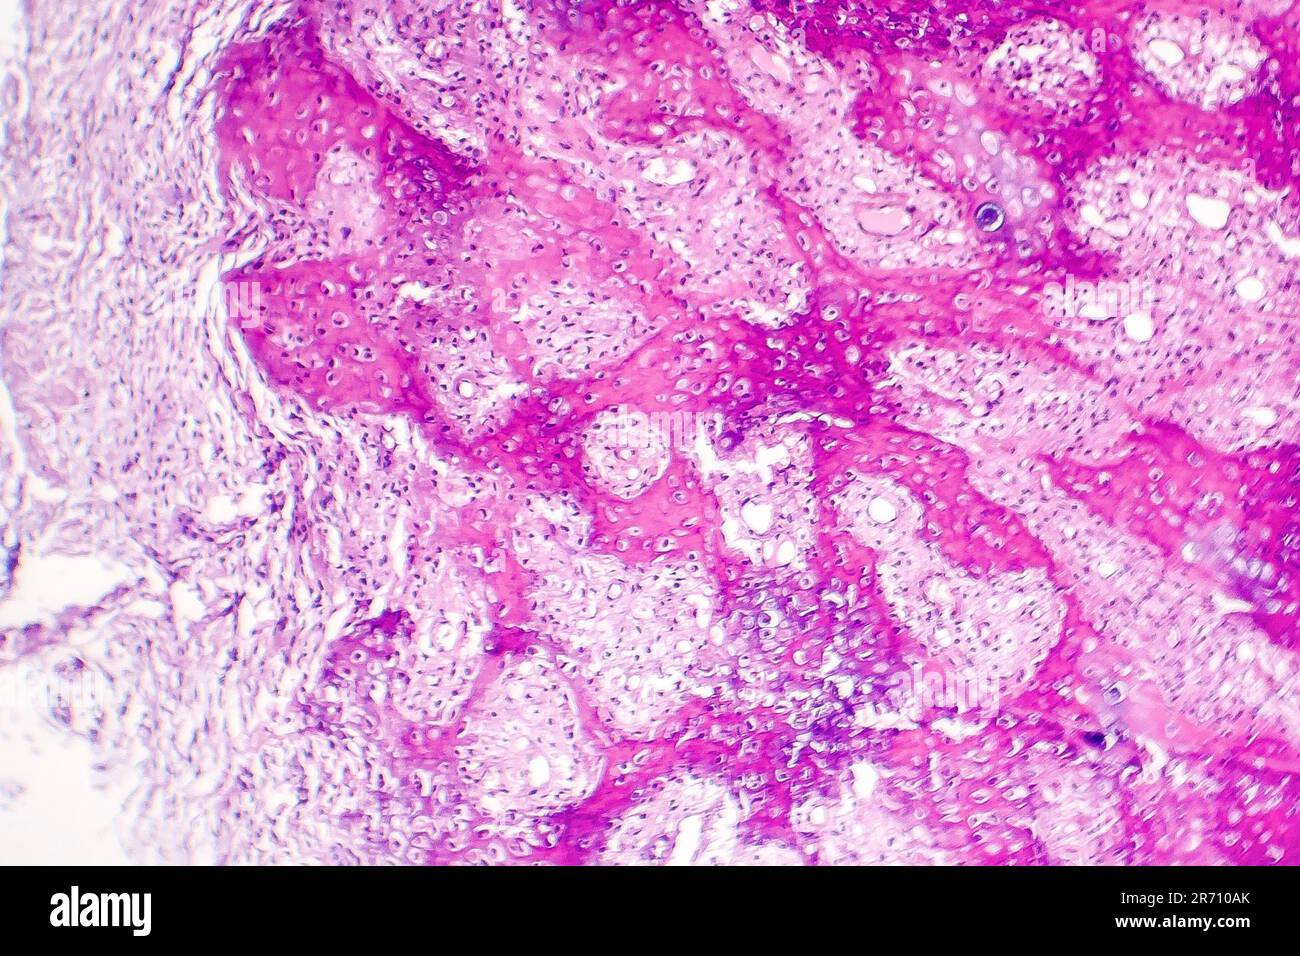

Histology of callus, a thickened skin made as a result of pressure Calluses In The Mouth what is leukoplakia? There are many types of this condition, including corns and calluses,. It has several possible causes, including repeated injury or irritation. a person with a mouth or tongue lesion may have lumps, bumps, little ulcers, or cuts inside or outside of their mouth and lips. irritation from masticatory function may cause frictional keratosis when. Calluses In The Mouth.